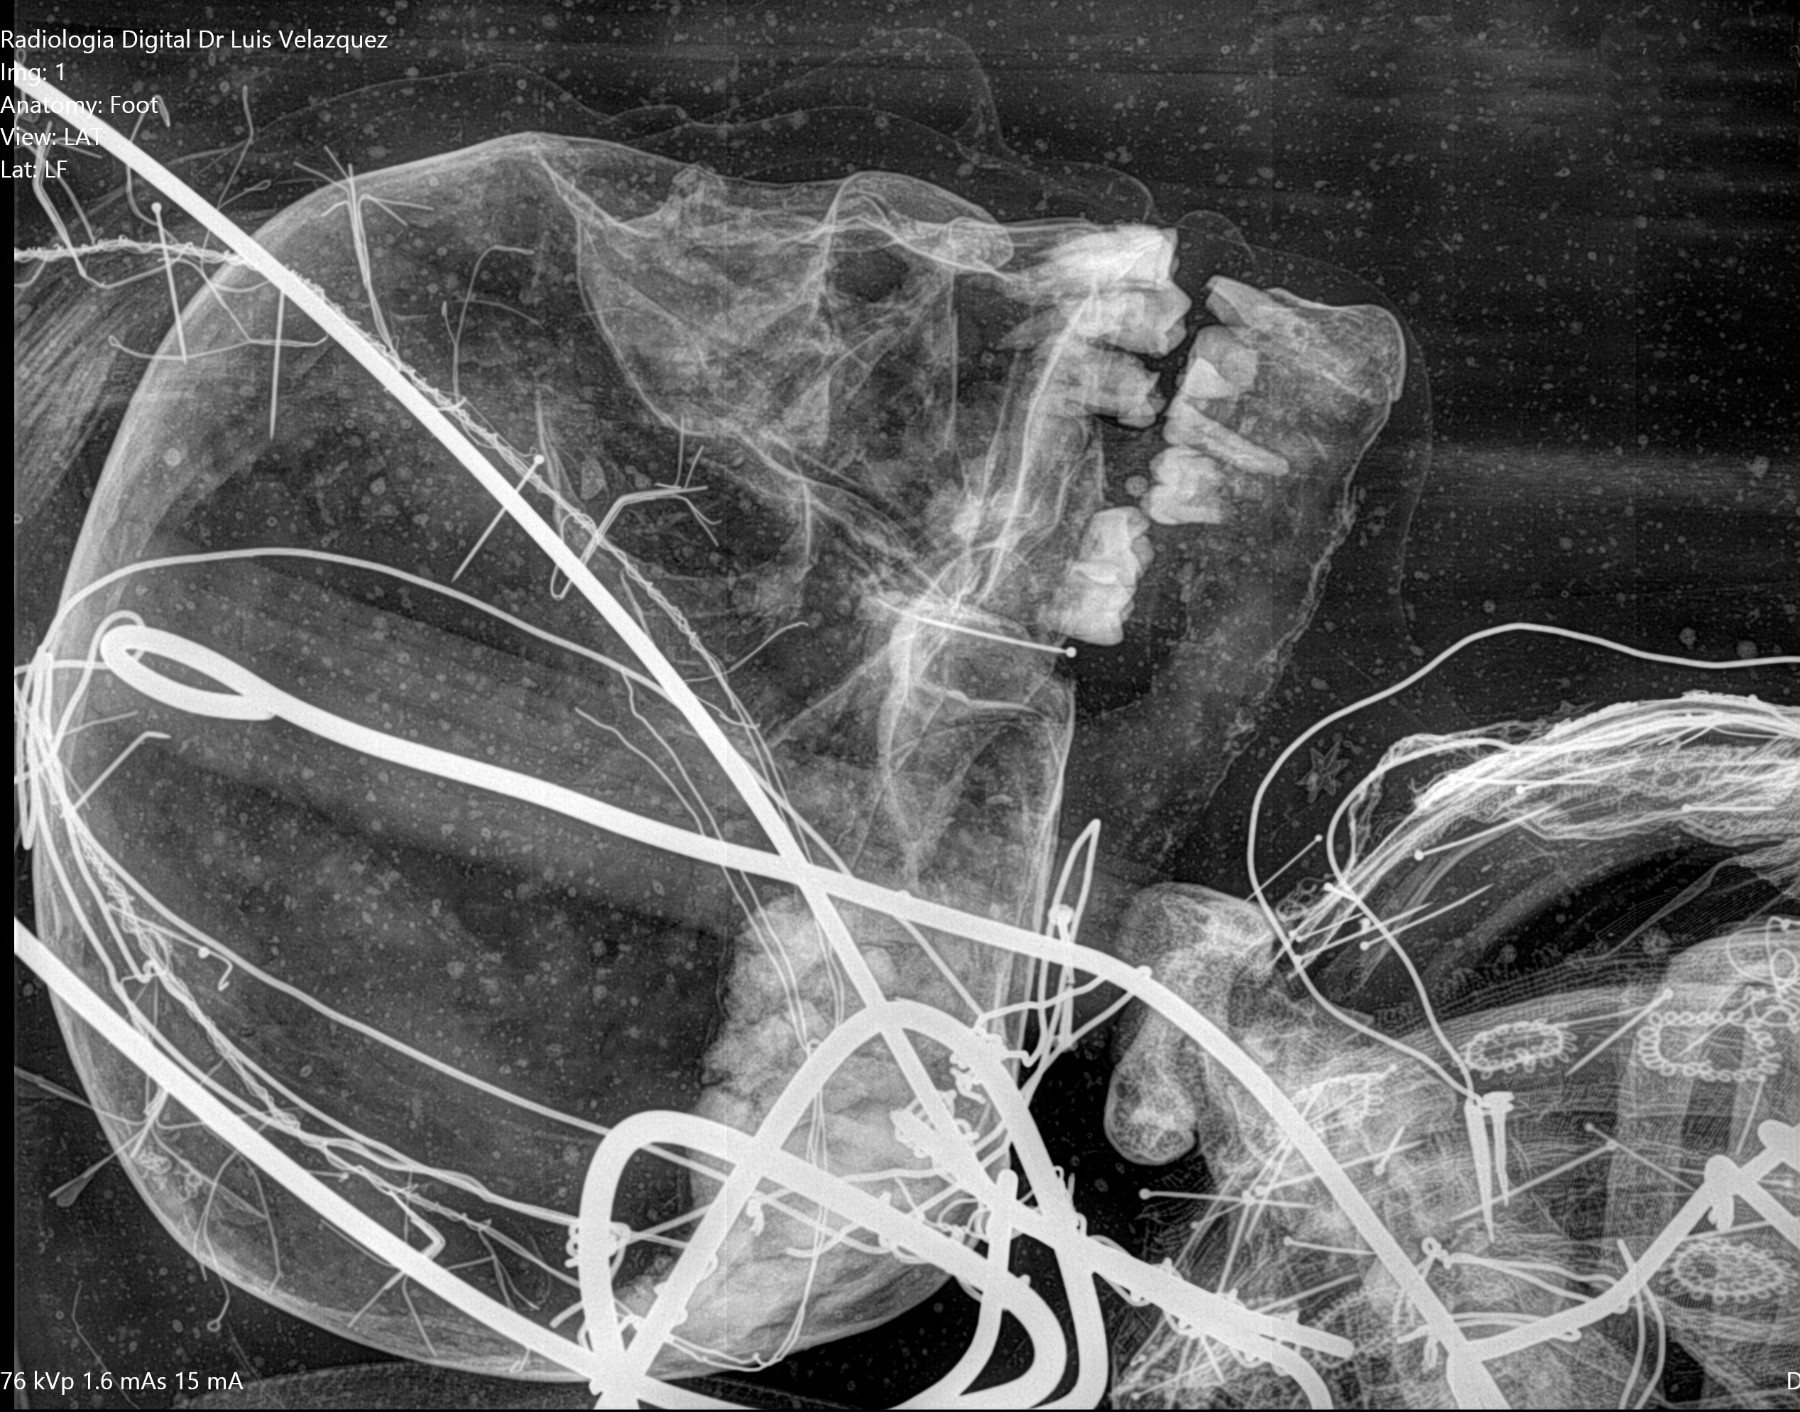

Cambios Térmicos en las Extremidades de Caballos,

Asociados a Golpes y su Evaluación por Termografía.

Los caballos de salto, en competencia, pueden derribar obstáculos y lastimarse. Si se golpean, no siempre claudican. Considerando al calor como un signo de inflamación, se evaluaron los cambios térmicos de 6 áreas de las extremidades torácicas y pelvianas de 23 caballos de salto en nivel de competencia de 1.05 a 1.60 m de altura, por medio de termografía durante 4 días de competencia (N=2208 áreas).